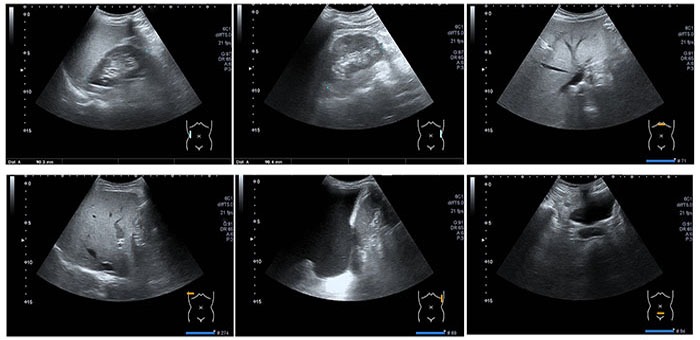

Ultrasound imaging of the abdomen uses sound waves to produce pictures of the structures within the upper abdomen. It is used to help diagnose pain or

distention (enlargement) and evaluate the kidneys, liver, gallbladder, bile ducts, pancreas, spleen and abdominal aorta. Ultrasound is safe, noninvasive

and does not use ionizing radiation.